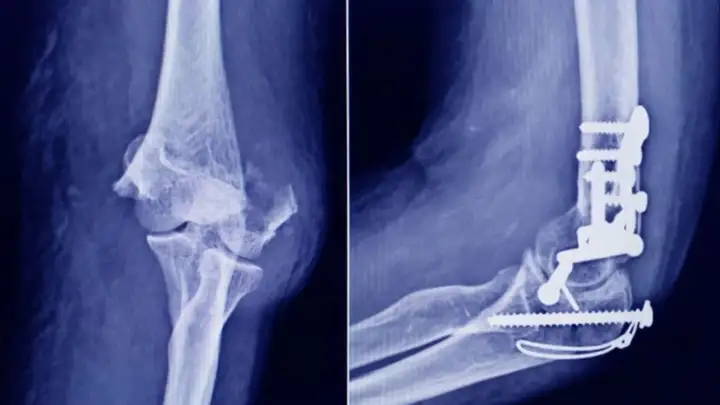

La Administración Nacional de Medicamentos, Alimentos y Tecnología Médica advirtió a la población por un tornillo utilizado en cirugías traumatológicas debido a que es falso, por lo que su uso representa riesgo para la salud del paciente al que se lo implante. Se trata de un producto que fue detectado durante una inspección de control de mercado realizada en una ortopedia ubicada en la ciudad de San Miguel de Tucumán.

Dicho tornillo es producido por la firma Stryker Corporation, que se encuentra registrada ante ANMAT bajo el PM 594-139. Luego de la inspección, se exhibió la muestra recolectada ante la responsable técnica de esa empresa, quien afirmó que se trataba de un producto falsificado.

Las autoridades de la ANMAT dieron a conocer las características del producto para su advertencia: STRYKER 10 mm X 28 mm - BIOABSORBABLE - ACL INTERFERENCE SCREW - REF 234-010-067 - LOT 90905.